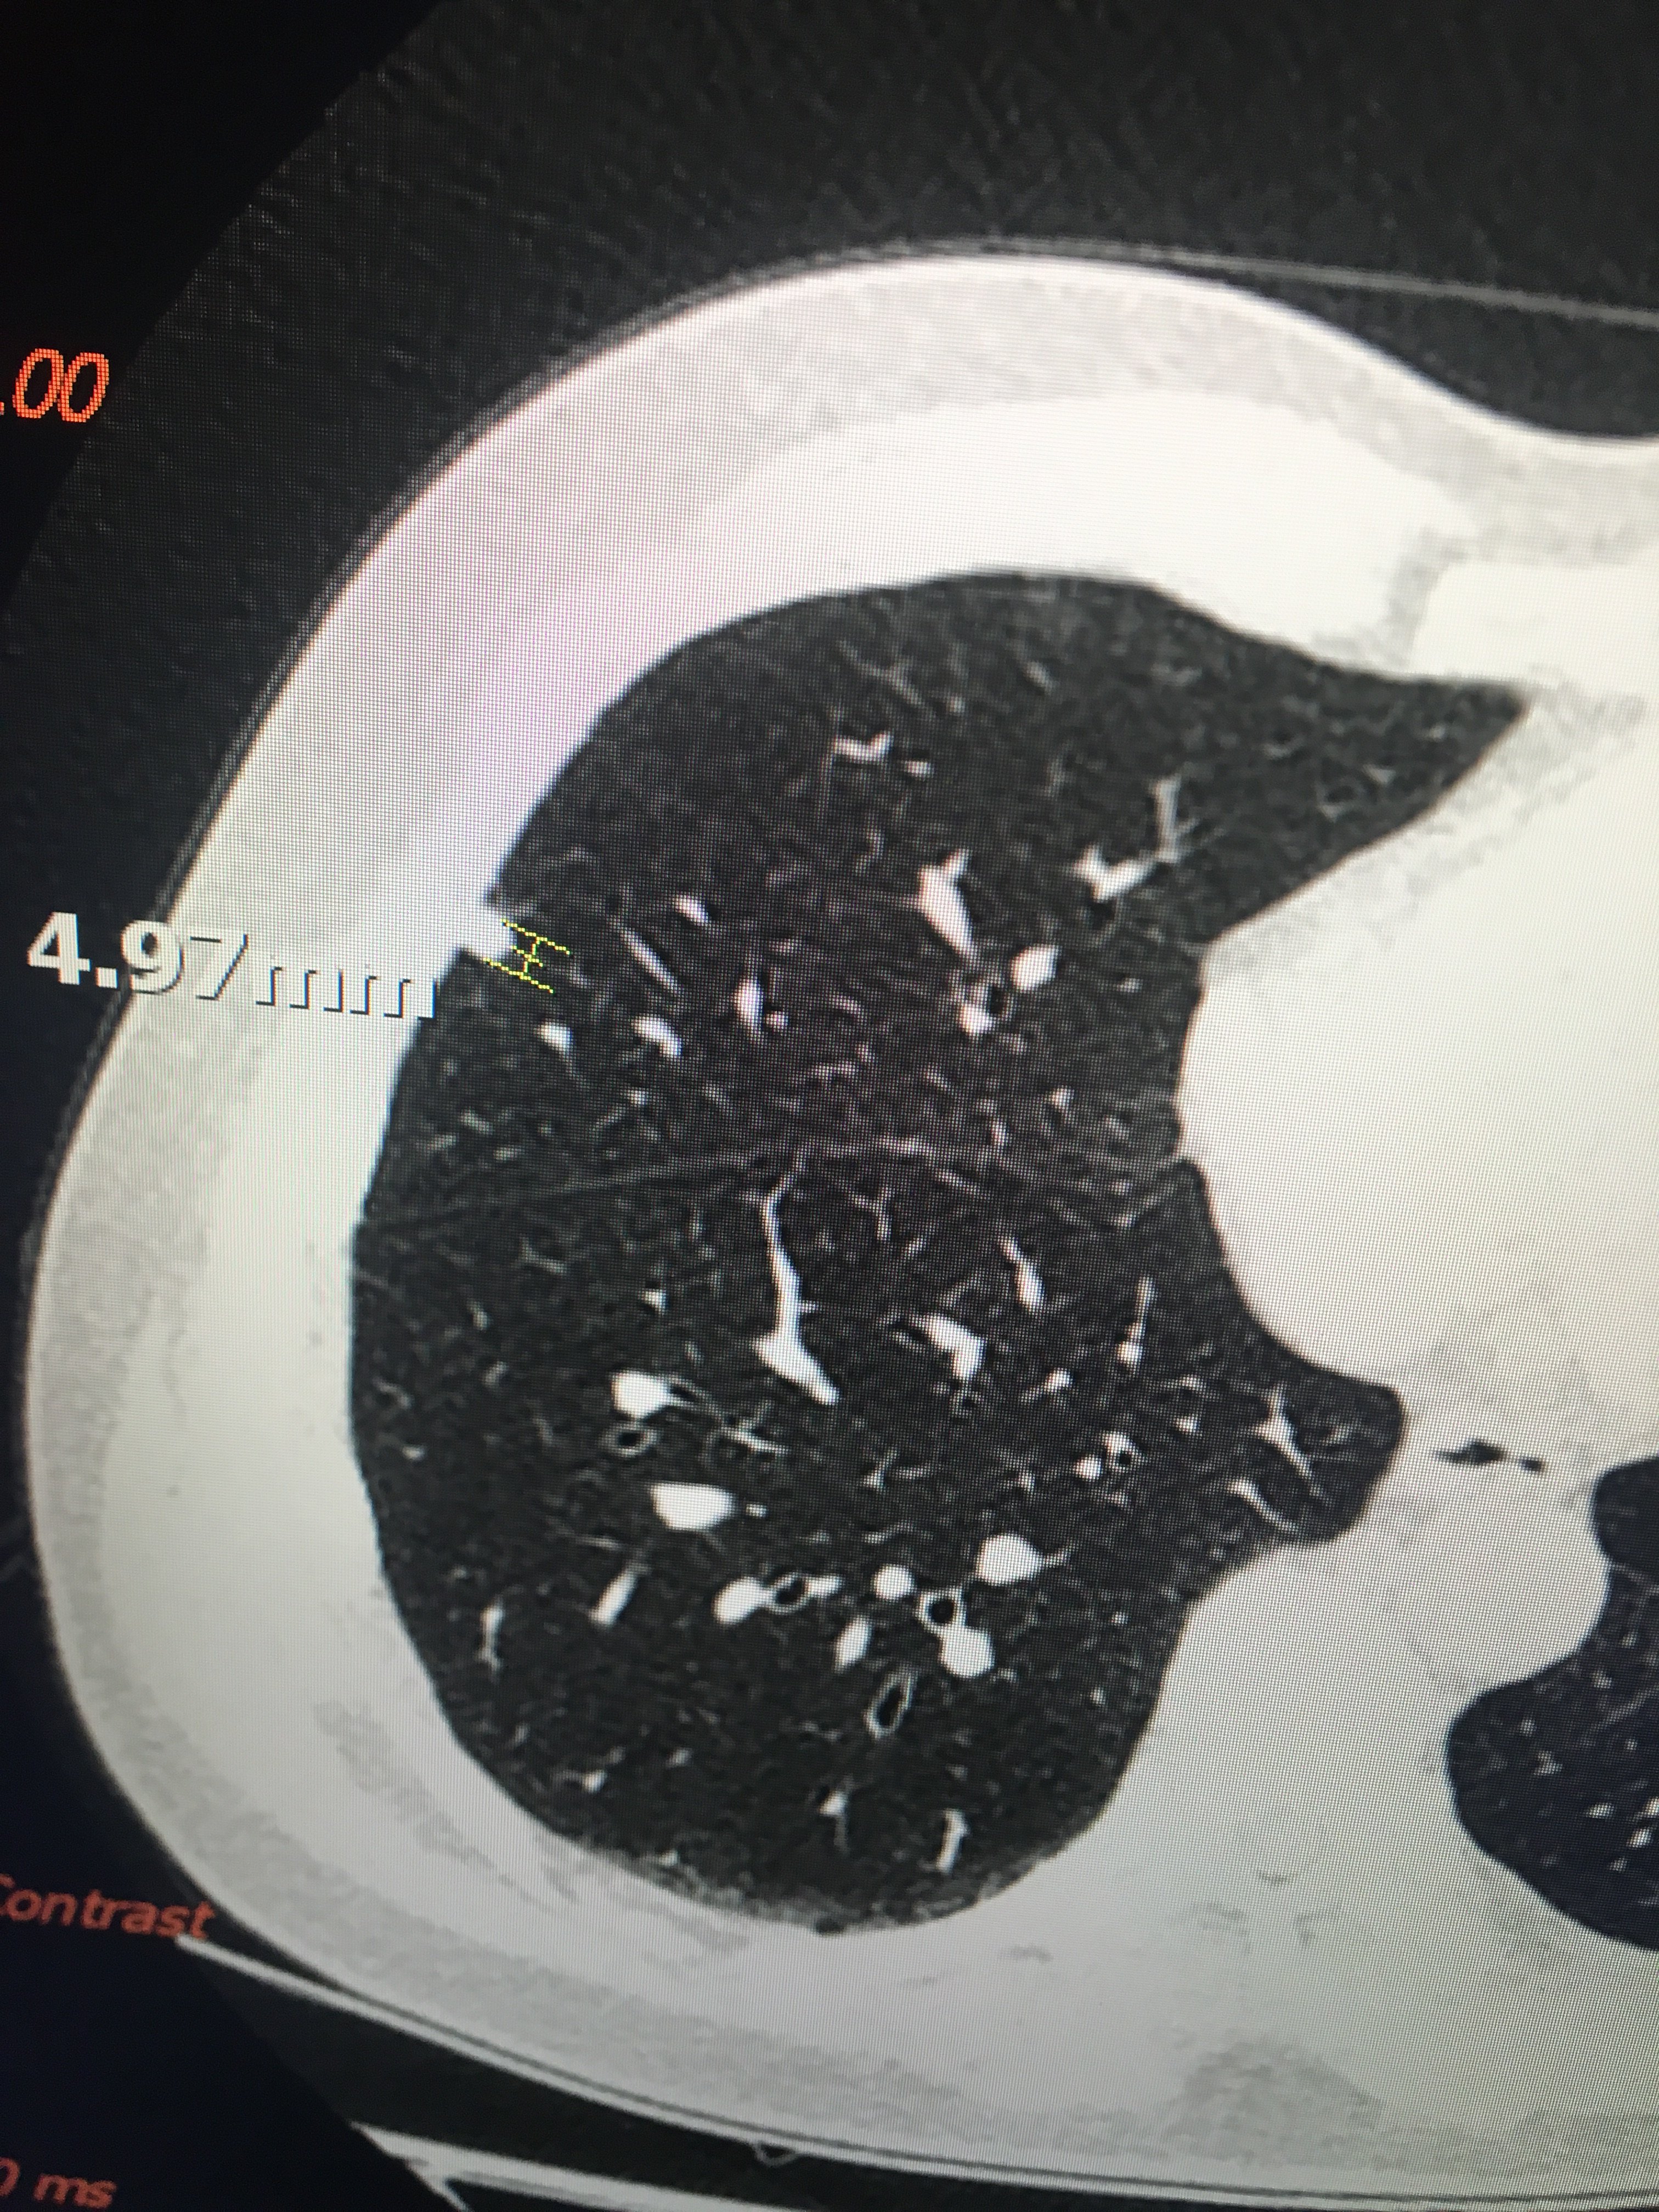

5mm磨玻璃结节

5mm肺磨玻璃结节需要立即手术吗?可以随访观察吗?

这是一位中年女士,体检发现5mm磨玻璃结节,随访观察3年没有明显进展